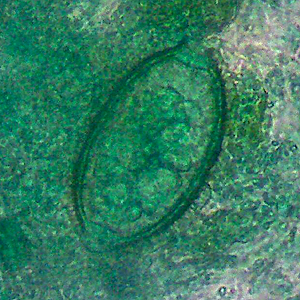

Case #343 – March, 2013

Stool specimens were collected from residents of the Peruvian Amazon rain forest to evaluate the burden of helminth infections. Stool was collected and processed via Kato Katz at a laboratory in Cusco, Peru. The objects in Figures A–C were observed in high numbers (1,500 eggs/gram of stool) from a 54-year-old male patient. The objects measured on average 65 micrometers long by 33 micrometers wide. Clinical examination of the patient revealed that he did not have eosinophilia or elevated liver enzymes. What is your diagnosis? Based on what criteria?

Figure A